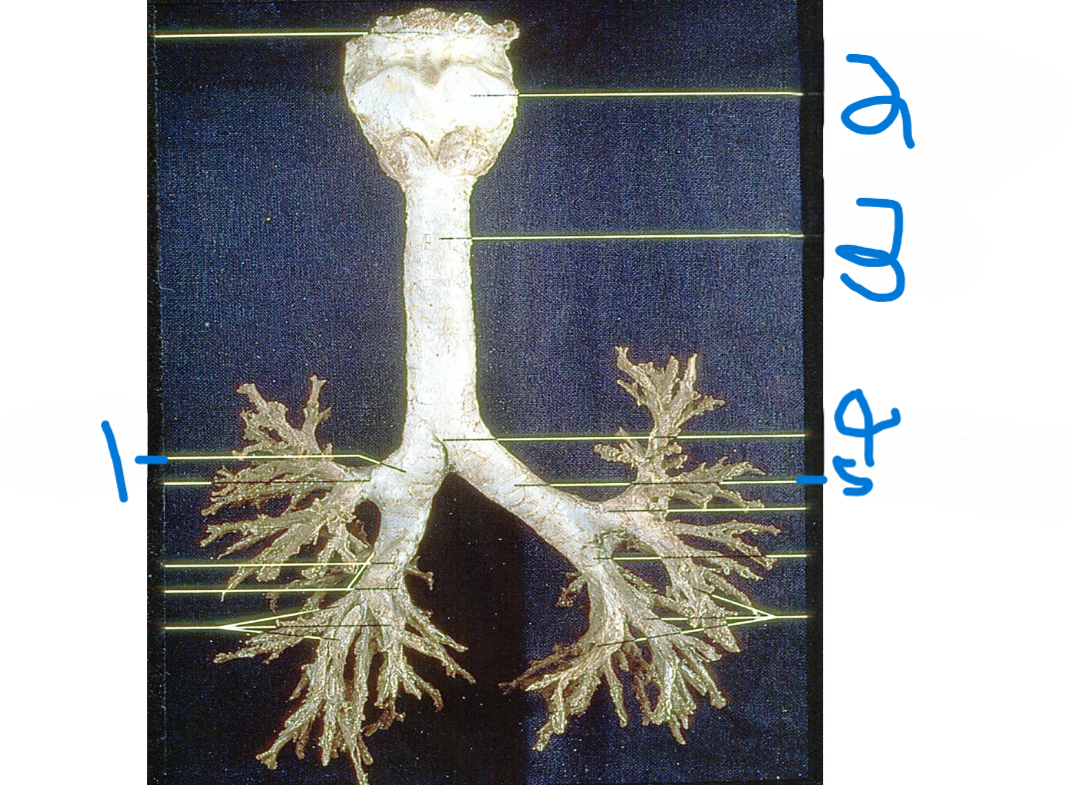

Right main bronchus

What is depicted by #1

Thyroid cartilage

What is depicted by #2

Trachea

What is depicted by #3

Carina

What is depicted by #4

Left main bronchus

What is depicted by #5